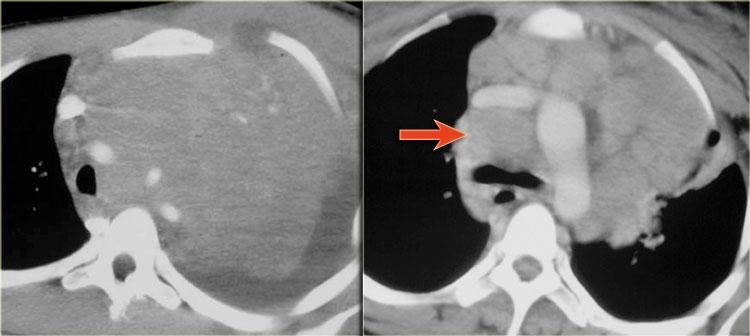

Phim ngực cho thấy các đặc điểm điển hình của u lympho Hodgkin, ví dụ: một khối trung thất trước.

Các hình ảnh CT của cùng bệnh nhân cho thấy một khối mô mềm lớn ở trung thất trước, xuất phát từ tuyến ức.

Có hạch cạnh khí quản kèm theo (mũi tên).

Hai trường hợp u lympho Hodgkin khác.

Các trường hợp này cũng cho thấy khối trung thất trước và hạch cạnh khí quản to.